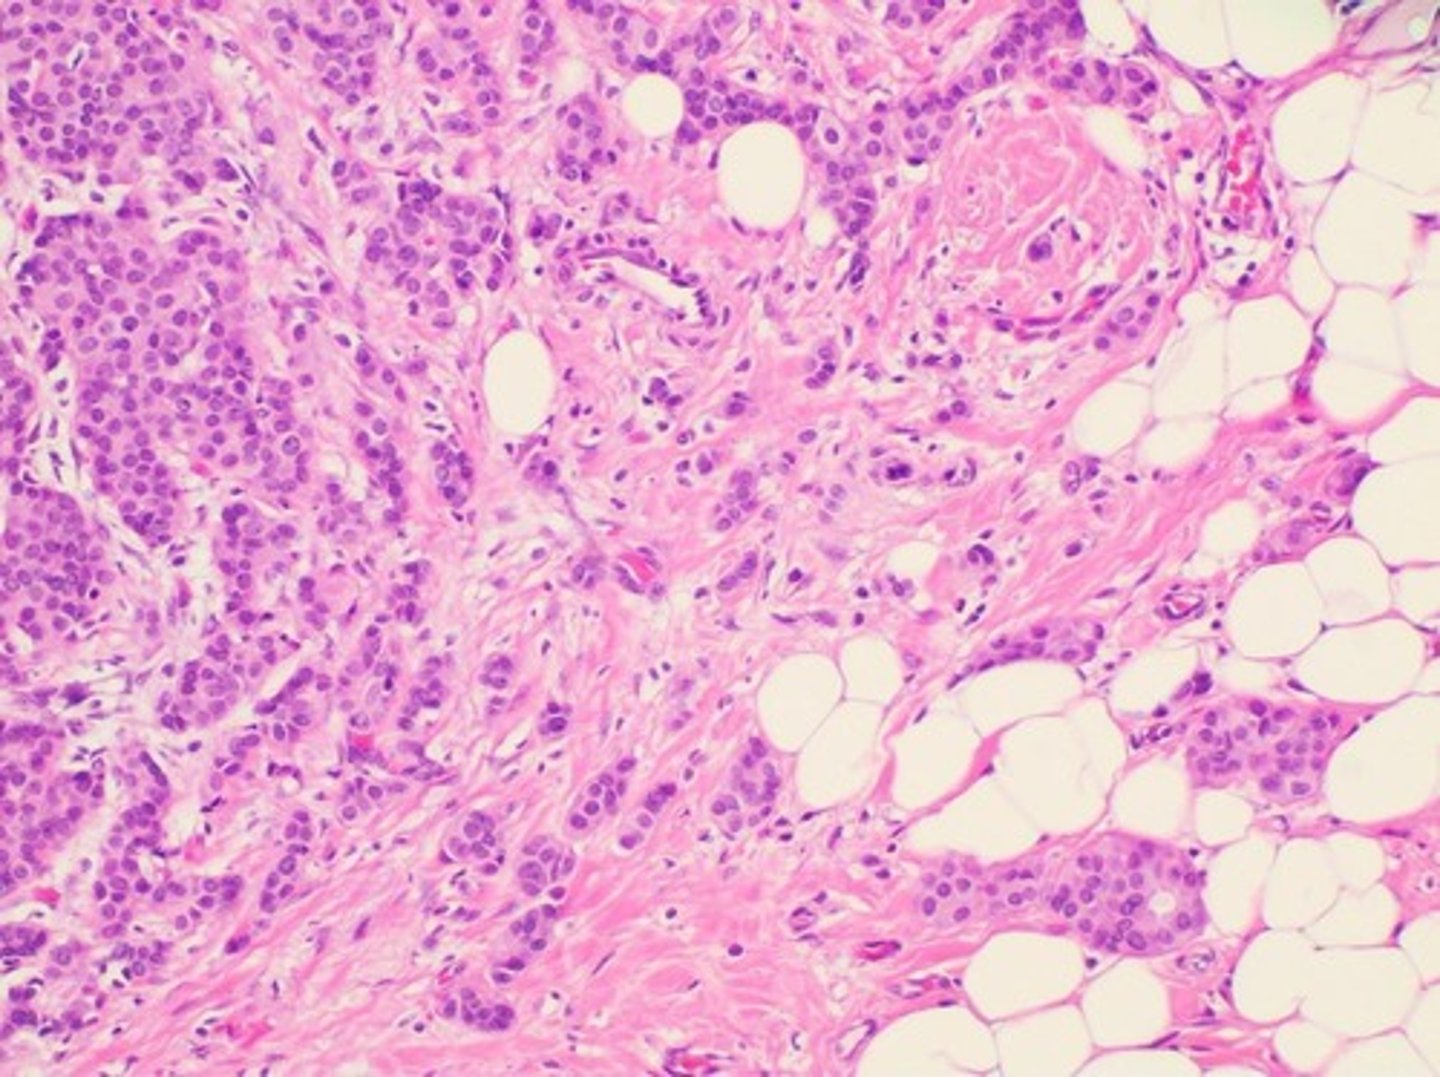

Cancer

Involves ECM remodeling for tumor growth and metastasis.

Pancreatic Cancer

Characterized by desmoplasia and ECM stiffening.

Desmoplasia

Excessive ECM deposition (fibronectin, collagen I/III) creates a dense, fibrotic barrier around the tumor.

MMPs

High levels of matrix metalloproteinases (MMP-2, MMP-9) degrade ECM locally, allowing tumor invasion.

Mechanotransduction

Stiff ECM activates integrins and FAK signaling, promoting tumor growth.

ECM Topography

Altered ECM topography enhances cell migration and metastasis.

Dense ECM

Limits drug delivery, reducing chemotherapy effectiveness.